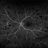

- Roth Spots, Optos, Retina, FLUORESCEIN ANGIOGRAPHY, left eye, Diabetes, ultra-wide field imaging

Scanning laser ophthalmoscope

Optos California - Description

- Roth spots during optos FA on a 68 year old female with retinal hemorrhage effecting her left eye. Patient was referred for non-proliferative diabetic retinopathy without macular edema.